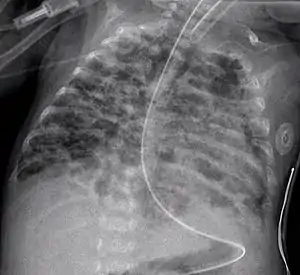

| An X-ray showing bronchopulmonary dysplasia. Person is also intubated and has an oral gastric tube. | |